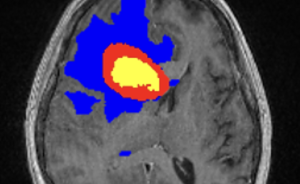

The HGG software analyzes brain tumor MRIs with the power of AI to guide clinicians in their treatment decisions, helping them to plan procedures accordingly, better evaluate post-procedural results, steer chemotherapy and immunotherapy treatments, and properly follow-up with patients during arduous recovery processes.